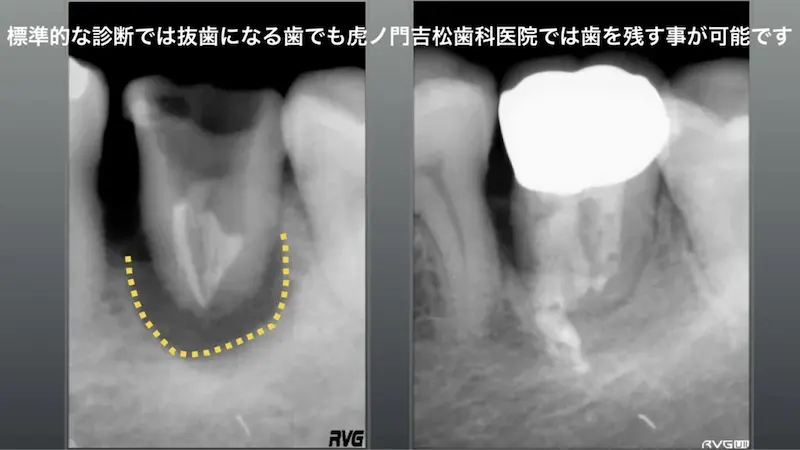

標準的な診断では抜歯になる歯でも

残すことが可能です

通常、根管内から破折線が確認された場合は抜歯の診断になりますが、清潔な環境にて感染部を除去し正確に接着できれば、歯を残す事が可能な場合が多くあります。